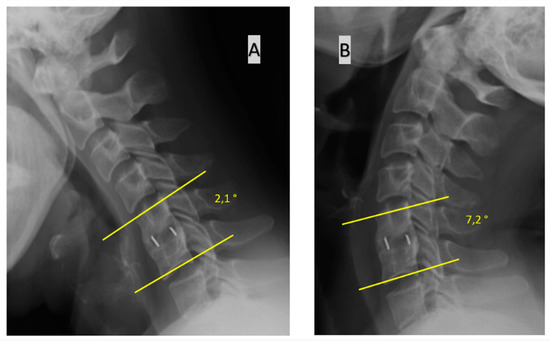

- change in the value of Cobb’s angle of the operated motion segment in flexion vs. extension. Changes <2° are a sign of fusion while changes ≥2° represent a pseudoarthrosis.

- change in the value of Cobb’s angle of the operated motion segment in flexion vs. extension, as in the 3rd method above, but with a different threshold: <4° is fusion and ≥4° is a pseudoarthrosis.